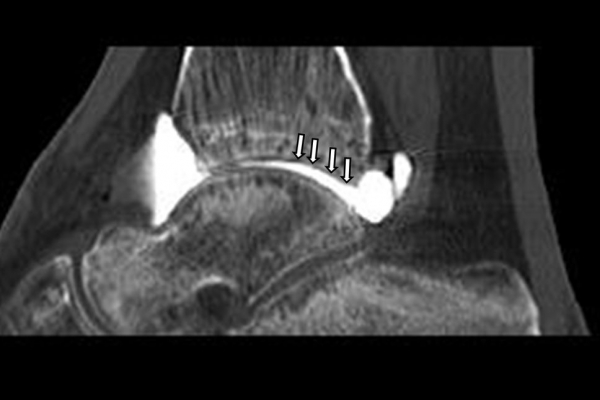

Είναι μια ελάχιστα επεμβατική απεικονιστική μέθοδος που επιτρέπει τη λεπτομερέστερη διερεύνηση του εσωτερικού των αρθρώσεων. Η ασφαλής έγχυση σκιαγραφικού εντός της άρθρωσης υπό ακτινολογική καθοδήγηση και η ακόλουθη απεικόνιση της άρθρωσης με αξονική ή μαγνητική τομογραφία (ή και με συνδυασμό των μεθόδων) αποσαφηνίζει βλάβες του χόνδρου και κακώσεις-ρήξεις συνδέσμων και τενόντων με υψηλή ακρίβεια, συμβάλλοντας σημαντικά στο λεπτομερή χειρουργικό σχεδιασμό.